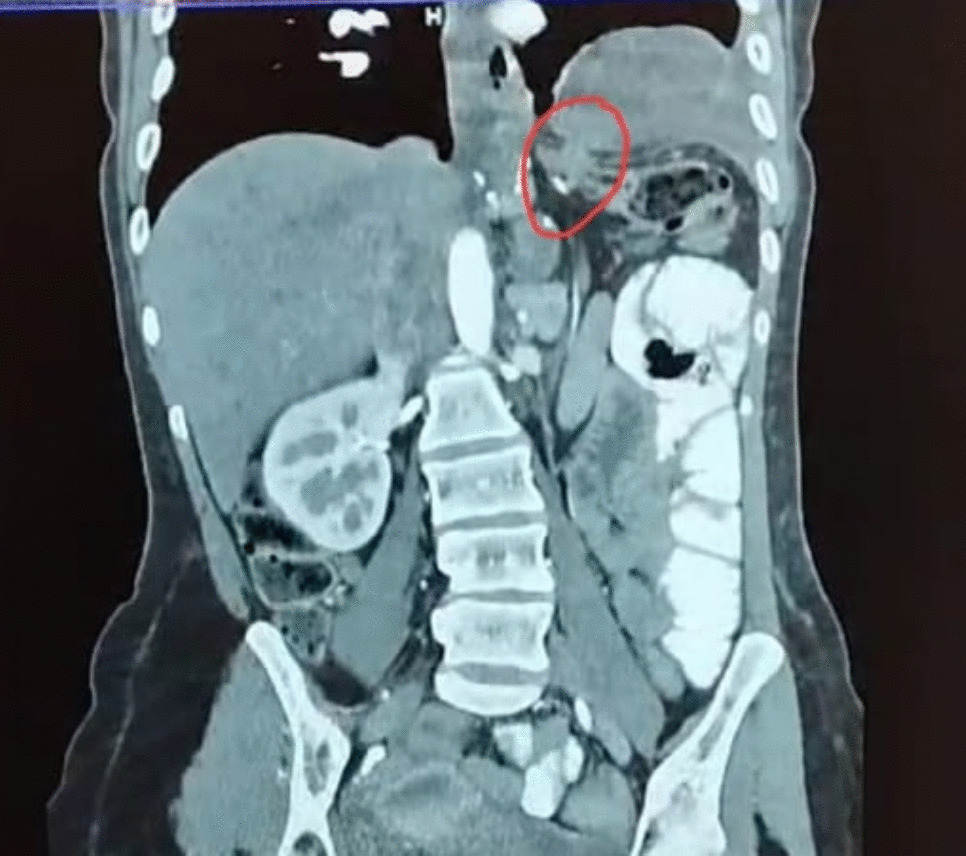

Laboratory tests revealed no significant findings apart from mild anemia and an elevated C-reactive protein (CRP) of 38 mg/L. A computed tomography (CT) scan of the abdomen and pelvis showed a hollow organ herniating into the left hemithorax, compressing the left lung with no intra-abdominal or thoracic collections (Fig. 1). After counseling the patient, the decision was made to proceed with laparoscopic exploration.

Fig. 1

CT chest and abdomen showing herniation of a hollow organ through a small diaphragmatic opening

In this case, the patient had chronic vague symptoms of epigastric pain, but what grabbed attention was the sudden onset of severe abdominal pain with tachycardia, raising suspicion of a more serious underlying condition. The CT scan confirmed the diagnosis of the herniated colon in the left hemithorax.